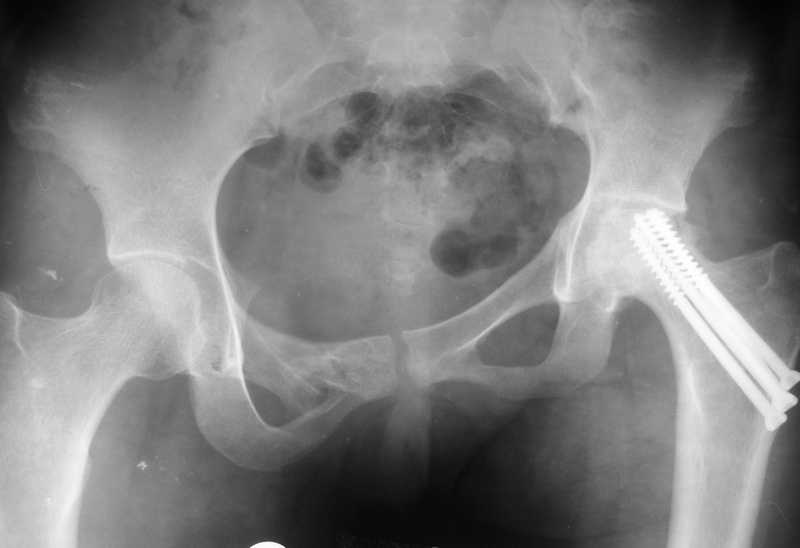

Через год стала ходить без палочки С марта 2009 года стала замечать укорочение левой нижней конечности

Запоздалое укорочение означает смещение вверх или отсутствия сращения в крестцово-подвздошном сочленении. Поэтому требуются стандартные снимки тазового кольца и Компьютерные Томографические исследования с возможностью 3Д реконструкции.

По первым снимкам имеется сложная травма с переломом ацетабулума (видна линия перелома в задней колонне) и таза с ипсилатеральным переломом шейки. Не удалось репонировать крестцово-подвздошное сочленение, и смещение с ротацией осталось, особенно в верхней ветви лонной кости. Клинические снимки подтверждают остаточную деформацию и укорочение конечности за счет таза.

Ипсилатеральные переломы ацетабулума и шейки бедра в большинстве случаев приводят к аваскулярному некрозу головки.

Все-таки основное укорочение за счет таза-смещение дна вертлужной впадины вверх порядка 3 см., плюс разворот, дающий приводящую контрактуру и укорочение еще 3-4 см.